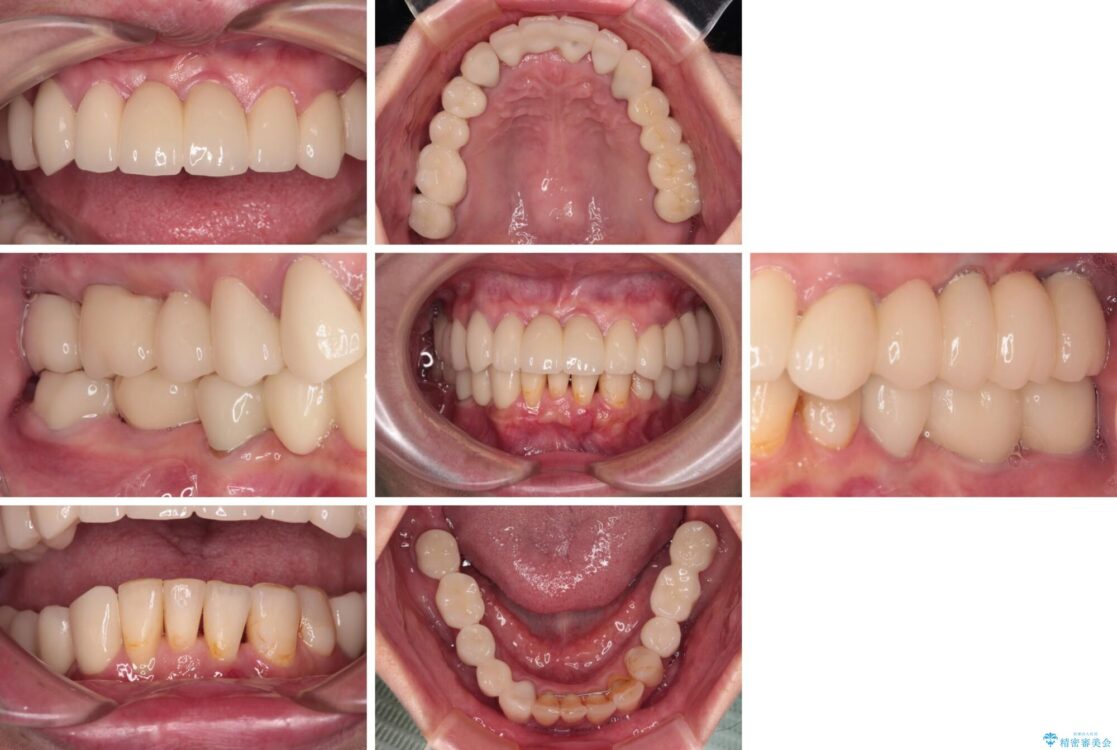

治療後

• 放置したインプラントとインビザライン 全顎リカバリー治療 治療後画像